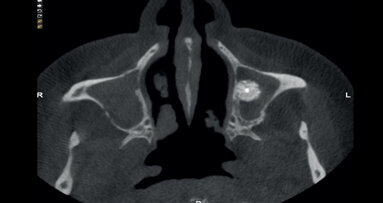

Fig. 3. Presencia del trayecto de la arteria.

El sangrado intraoperatorio resulta de dañar las ramas vasculares de la pared lateral del seno y de los tejidos blandos circundantes. También existe la posibilidad del sangrado desde una anastomosis extra ósea de la arteria alveolar superior posterior y la arteria infraorbitaria durante la elevación del colgajo y desde la arteria nasal lateral posterior. Para evitar una laceración de esta anastomosis y una vez se prevé la posibilidad de que exista una complicación hemorrágica, es prudente localizar la posición de la arteria en las imágenes de corte transversal del CBCT y luego utilizar un abordaje que respete la integridad de los tejidos.